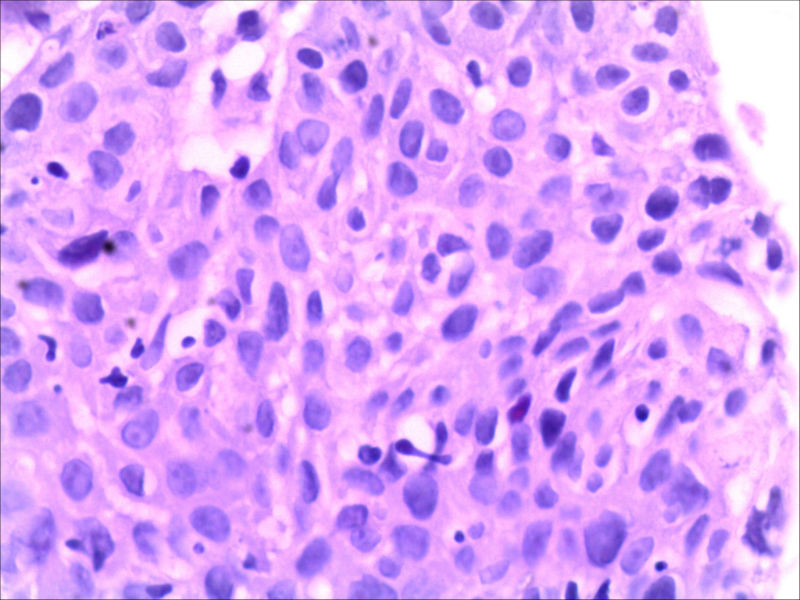

食管活检男64岁食管粗糙

高级别上皮内瘤变,取材表浅,不排除高分化鳞癌,请结合临床建议必要时再取活检

同意,本例仅出现食管黏膜粗糙,如果没有较大肿块或溃疡,也有可能就是个高度上皮内瘤变或早期食管癌。因此可做超声内镜,如果可能,做大黏膜切除治疗。

新版WHO分类中指出:食管和胃内“上皮内瘤变”和“异型增生”都可以用,关键是要与临床沟通好,让其知道二者之间的对应关系和处理原则。

高度上皮内瘤变的适用范围大于重度异型增生/原位癌。